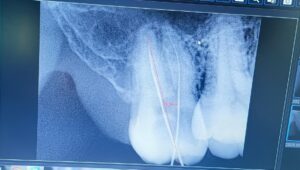

Home Dentistry Doctors Our Events Dengue Awareness Session MoU Signing Ceremony of Life Care Medical and Dental Center with Shahab Orthopedic Hospital Peshawar Patient Cases About Us Health Care Commission KPK Doctor’s Profiles X Book An Appointment “Our Patient SuccessStories” Australian Casino Payment Options View Case Austrlian online casinos guide View Case Austrlian online casinos guide View Case Best Online Casinos in Canada View Case Patient Cases Division 1 Malocclusion with Premolar Extraction View Case Patient Cases Root Canal Treatment – Asad, Age 27 View Case Lorem ipsum dolor sit amet, consectetur adipiscing elit. Ut elit tellus, luctus nec ullamcorper mattis, pulvinar dapibus leo. Company About Us Leadership History Careers Legal Notice Support Contact Us FAQ Get an Appointment Help Center Ticket System Location help@lcmdc.com 0314-0984321